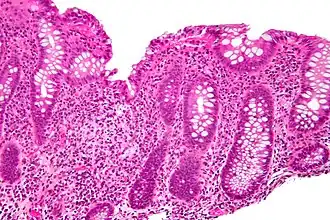

-

Cryptitis. H&E stain. -